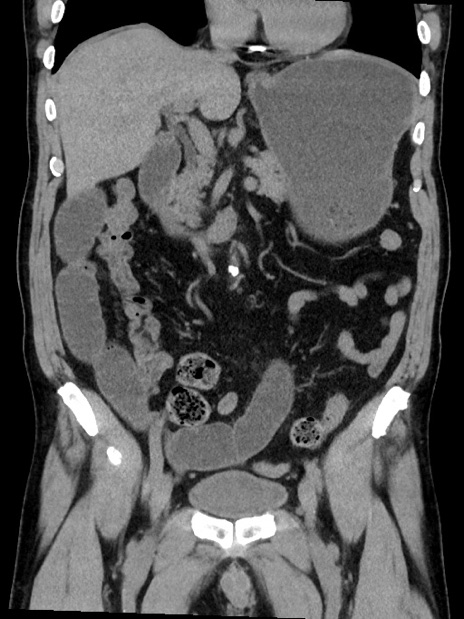

症例35(冠状断像)

【症例】70歳代 男性

【主訴】腹部膨満、嘔吐

【現病歴】昨日より腹部膨満感出現。本日増悪し、仙痛出現。嘔吐あり、受診。

【既往歴】糖尿病、胆摘後

【身体所見】BP 149/80mmHg、HR 74/min、BT 35.9℃、腹部:膨満、軟、圧痛なし。腸雑音減弱あり。上腹部正中切開瘢痕あり。

【データ】WBC 13500、CRP 1.72